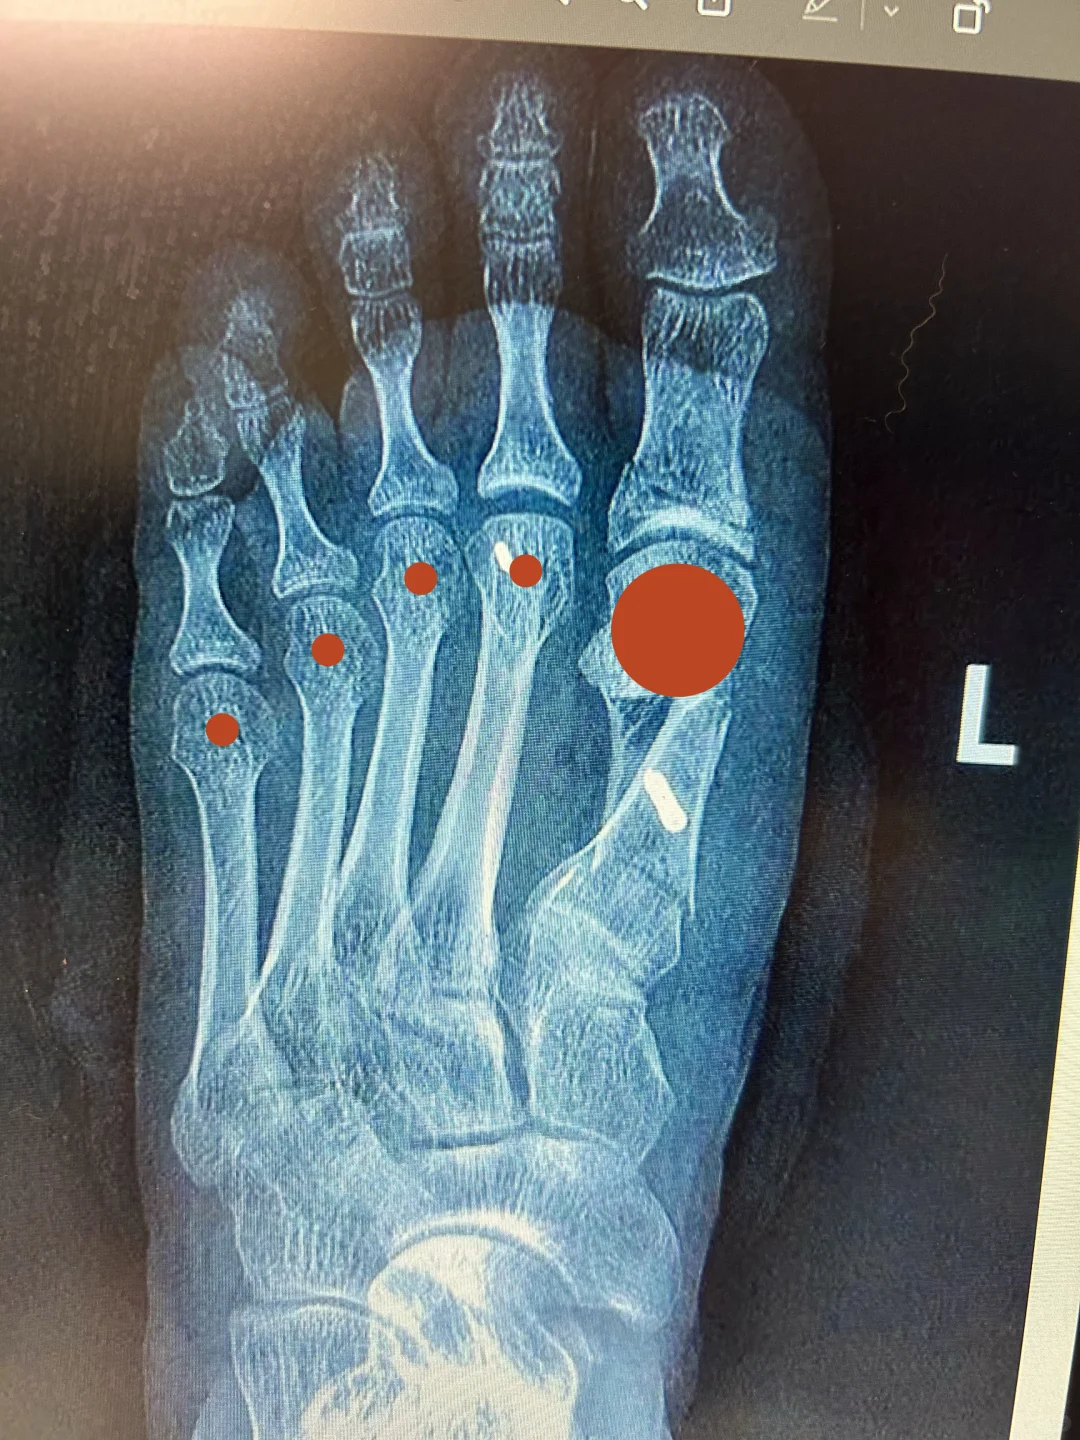

[四R] 图4大红点区域是跖骨头的位置,这个位置不应该有断骨,不应该有螺钉,应该维持原装态。不然容易影响血运,而且松质骨也不结实。对,Chevron截骨直接出局。

[五R] 螺钉或者吸收钉固定,除小趾外不能用克氏针。更不能有任何穿关节固定,不能有任何关节融合,毕竟手术的目标是无限接近正常足,无论功能、外观、还是骨结构。

[六R] 最后看1.2.3.4跖骨头的距离比较匀称,而不是1.2间隙大于2.3间隙,靠分趾垫维持拇趾变直。有的断骨推移不够,长期夹分趾器也能维持不错外观,很容易迷惑他人。